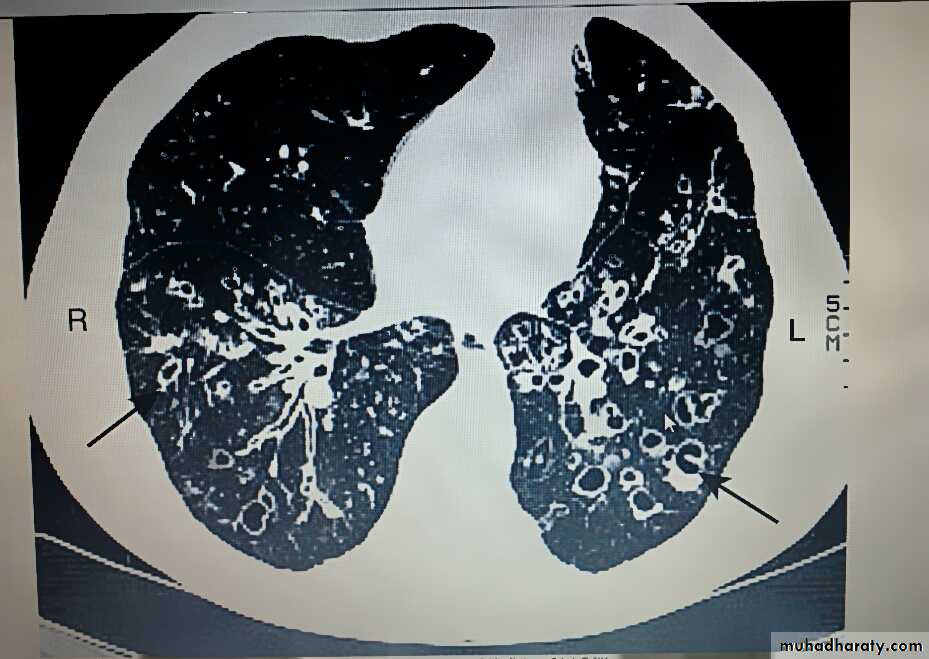

2)Radiological examination

Bronchiectasis, unless very gross, is not usually apparent on a chest X-ray. In advanced disease, thickened airway walls, cystic bronchiectatic spaces, and associated areas of pneumonic consolidation or collapse may be visible. CT is much more sensitive, and shows thickened dilated airways.